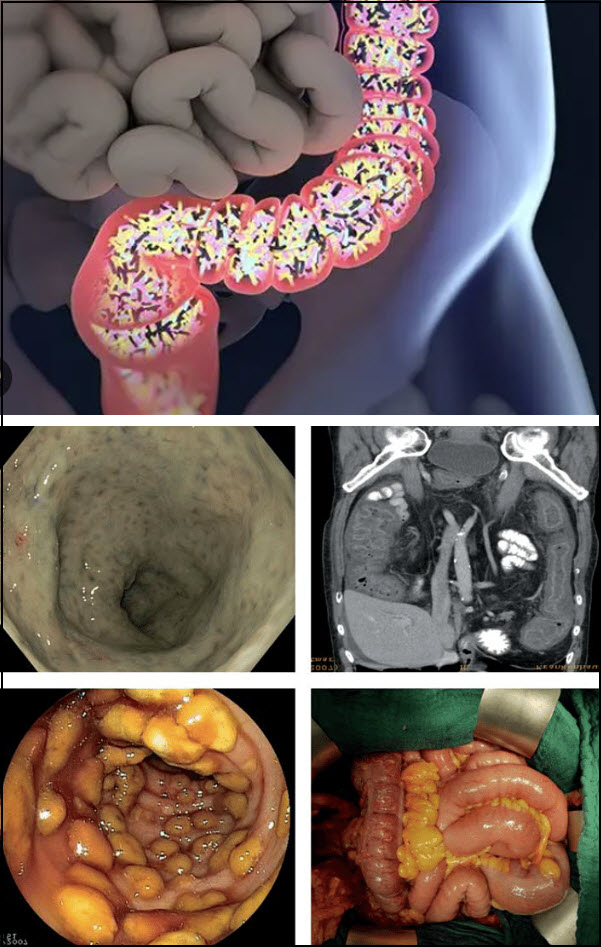

Crohn hastalığı Crohn’s Disease

Crohn hastalığının tedavisi yoktur..ve Crohn hastalığının kesin nedeni bilinmemektedir…) Kaynak Birleşik Krallık Ulusal Sağlık Hizmeti ( NHS )

Crohn hastalığı, sindirim sisteminin bazı kısımlarının iltihaplandığı yaşam boyu süren bir durumdur. İnflamatuar bağırsak hastalığı (IBD) adı verilen bir durum türüdür…) Crohn hastalığı için tedaviler..Crohn hastalığının tedavisi yoktur, ancak tedavi semptomlarınızı azaltmanıza veya kontrol etmenize yardımcı olabilir...)Crohn hastalığının nedenleri Crohn hastalığının kesin nedeni bilinmemektedir...)Kaynak Birleşik Krallık Ulusal Sağlık Hizmeti ( NHS )

Kalıtım. Crohn’s, hastalığı olan aile üyeleri olan kişilerde daha yaygındır, bu nedenle genler, insanları daha duyarlı hale getirmede rol oynayabilir. Bununla birlikte, Crohn hastalığı olan çoğu kişinin ailesinde hastalık öyküsü yoktur. Crohn hastalığı, bir tür inflamatuar bağırsak hastalığıdır (IBD). Karın ağrısına, şiddetli ishale, yorgunluğa, kilo kaybına ve yetersiz beslenmeye yol açabilen sindirim sisteminizin iltihaplanmasına neden olur…)Kaynak 2022 Mayo Tıp Eğitimi ve Araştırma Vakfı (MFMER).

Crohn hastalığının nedenolduğu iltihaplanma, farklı insanlarda sindirim sisteminin farklı alanlarını içerebilir. Bu iltihaplanma genellikle bağırsağın daha derin katmanlarına yayılır. Crohn hastalığı hem ağrılı hem de güçten düşürücü olabilir ve bazen yaşamı tehdit eden komplikasyonlara yol açabilir…)Kaynak 2022 Mayo Tıp Eğitimi ve Araştırma Vakfı (MFMER).

Teşhis

Kolonoskopi..Bilgisayarlı tomografi (CT)…)Kaynak 2022 Mayo Tıp Eğitimi ve Araştırma Vakfı (MFMER).

Ameliyat

Diyet ve yaşam tarzı değişiklikleri, ilaç tedavisi veya diğer tedaviler belirtilerinizi ve semptomlarınızı gidermezse, doktorunuz ameliyat önerebilir. Crohn hastalığı olanların yaklaşık yarısı en az bir ameliyat gerektirecektir. Bununla birlikte, cerrahi Crohn hastalığını iyileştirmez…)Kaynak 2022 Mayo Tıp Eğitimi ve Araştırma Vakfı (MFMER).

Crohn hastalığı için ameliyatın faydaları genellikle geçicidir. Hastalık sıklıkla yeniden bağlanan dokunun yakınında tekrarlar. En iyi yaklaşım, tekrarlama riskini en aza indirmek için ameliyatı ilaçla takip etmektir...)Kaynak 2022 Mayo Tıp Eğitimi ve Araştırma Vakfı (MFMER).